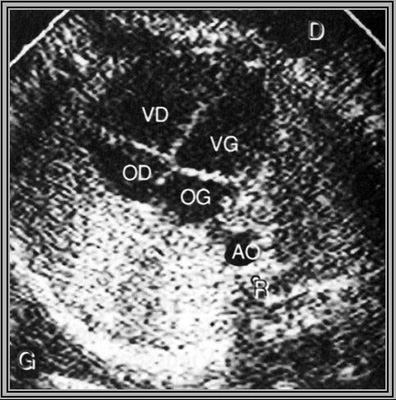

Concordance auriculo-ventriculaire

4 cavités